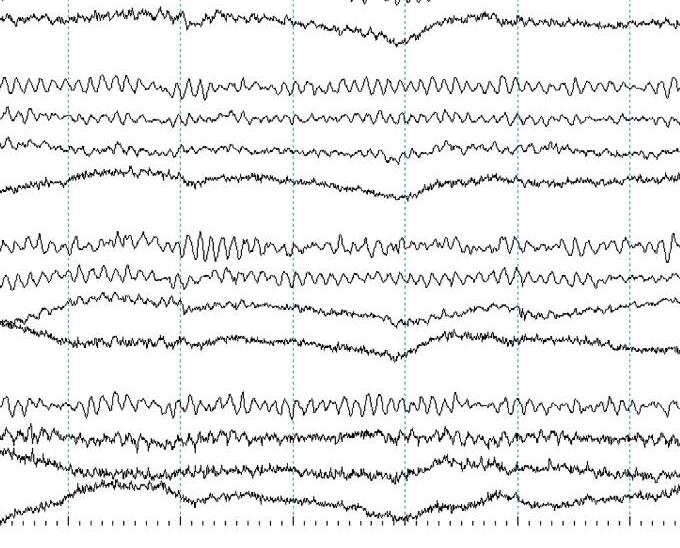

Display(Parameters) Atypicalbedsidedisplayusingalongitudinalbipolarmontageisshownin Figure1.3(a). Variationstothisformatexist.Commonly,theleftandtheright temporalchainsarestackedtogetherfollowedbytheleftandrightparasagittal chains.Thismakesiteasytocomparethetemporalandparasagittalregionsof bothhemispheresforasymmetry.Readersshouldknowthatthetemporal regionsarealsothemostepileptogenicsofocusingonthesechannelsyields results!Thetopbarofarecordingshowsthesensitivity,filtersettings,and timebase.

Mostdisplaysshow10or15secondsperpageofEEG. Figure1.5 showsa typicaldisplayusingthelongitudinalbipolarmontagewithexcessivemuscle artifactbefore(a)andafter(b)applicationof30Hzhighfrequencyfilter.

Figure1.5(b) ThesameEEGwithHFFsetto30Hz.